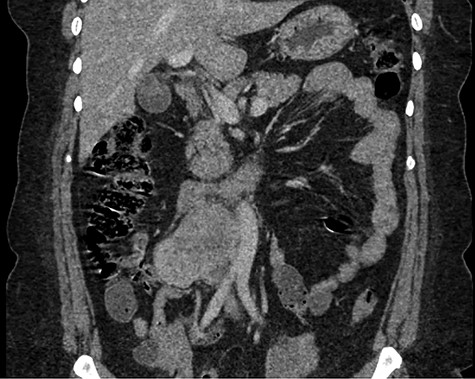

Abdominal CT demonstrating the location of the tumor in the IVC.

The patient had a body mass index of 40, so combined with her presentation, age and gender. The presumptive diagnosis was of gallbladder pathology, which prompted an abdominal ultrasound. Ultrasound revealed a large 7.7 × 6.3 × 7.2 cm heterogenous, hypoechoic masslike lesion overlying the IVC (Fig 1). Abdominal CT was performed, which revealed an 8.9 × 7.9 × 9 cm multilobulated, heterogeneous soft tissue mass in the right hemiabdomen, encasing the IVC and partially encasing the distal abdominal aorta (Figs. 2–4). CT-guided biopsy was performed, which revealed an LMS.